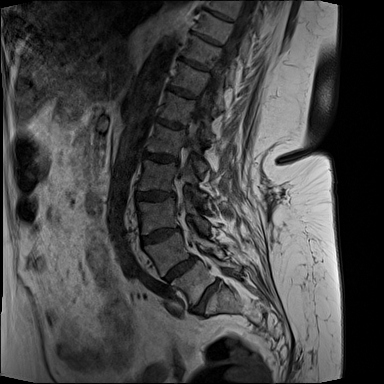

MRT Lendenwirbelsäule + Röntgen Becken - Diagnostik vor OP-Planung

MRT LWS (Lendenwirbelsäule)

DICOM

Magnetresonanztomographie der Lendenwirbelsäule (71 Bilder).

19.01.2024

MRT Lendenwirbelsäule (LWS)

71 Bilder | 1024x1024 px | 15 MB

MRT LWS

71 Bilder

Januar 2024

MRT LWS + Röntgen Becken

MRT der Lendenwirbelsäule und Röntgen des Beckens zur Diagnostik

MRT mit 71 Bildern